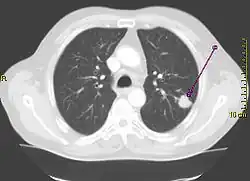

Рентгенограмма грудной клетки, демонстрирующая солитарный лёгочный узел в верхней доле левого лёгкого. | |